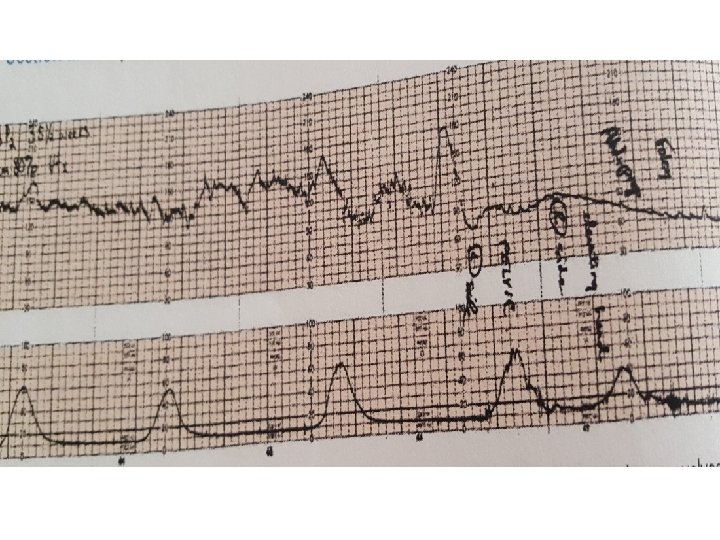

Variable Deceleration Abrupt decrease in FHR of > 15 beats per minute measured from the most recently determined baseline rate. The onset of deceleration to nadir is less than 30 seconds. The deceleration lasts > 15 seconds and less than 2 minutes. A shoulder, if present, is not included as part of the deceleration. Variable decelerations may be observed in up to 50% of NSTs. If nonrecurrent and <30 seconds, they are of no clinical significance.

Variable Deceleration Typical: • shoulders Atypical : • Overshoot • Loss of primary shoulder • Slow return to baseline (late component) • Baseline returns to a lower level(after deceleration) • Biphasic(W shape) • loss of variability during deceleration

Classification severity of variable deceleration • Mild: duration < 30 second or depth up to 80 bpm • Moderate : deceleration < 80 bpm • Severe : deceleration < 70 bpm for more than 60 second

Complicated variable deceleration Indicated fetal hypoxia • Tachycardia • Lack of variability • Slow return to baseline • Large amplitude(to 60 bpm or duration 60 second) • Loss of pre and post shouldering • Smooth overshoot